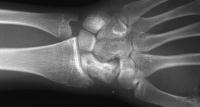

Healed.

The patient requested hardware removal prior to enlisting for military duty. Final films.